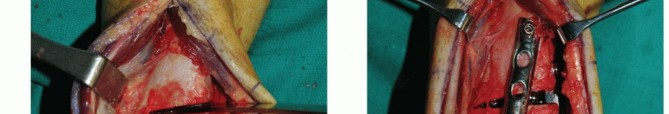

It is unlikely that a perfect clinical and fluoroscopic match will be achieved. Attempt to achieve the best clinical match of the graft's articular surface with the surrounding native cartilage (TECH FIG 4A).

We routinely secure the graft with one or two small-diameter solid screws (1.5 or 2.0 mm in diameter). One is typically placed from dorsal to plantar and the other from medial to lateral (if the depth of the graft will allow) (TECH FIG 4B,C).

Place the screws in lag fashion.

Countersink the screw heads below the articular surface (TECH FIG 4D,E).

Using fluoroscopy, confirm that the graft and hardware are in optimal position (TECH FIG 4F-H).

The graft will not look perfect fluoroscopically, but as long as the clinical appearance is acceptable, the outcome has a good chance to be favorable.

The hardware may appear slightly proud fluoroscopically despite being countersunk. The talar dome is not a flat plane, and therefore the screw may seem to be protruding. Moreover, the articular cartilage is rather thick compared to such a low-profile screw head.

- TECH FIG 4 • A-C. Fitting and securing the graft to the native talus. A. After contouring the graft (some minor discoloration from debris while manipulating graft on back table; it is easily washed away). B. Drill hole perpendicular to graft. C. Securing graft with two countersunk screws. (continued)

- TECH FIG 4 • (continued) D,E. A different patient with similar graft, excellent interference fit, and secured with a single screw. D. Screw is inserted in lag fashion. E. Screw head is countersunk. F-H. Reduction of the medial malleolar osteotomy. F. Screw fixation through the predrilled holes. G. Antiglide plate. H. Final fluoroscopic evaluation of graft and reduction of medial malleolar osteotomy. Despite optimal clinical fit of the graft, rarely does the fluoroscopic appearance suggest anatomic graft match to the native talus, typically due to differing cartilage thicknesses between the donor and the host. Although the screws may appear prominent, two-dimensional fluoroscopy is deceiving because the screws are countersunk below the articular surface of the graft and the talar dome is curved.

Fixation of the graft to the native talus (TECH FIG 9C-G)

We routinely use two solid small-diameter screws (1.5 or 2.0 mm) placed in lag fashion to secure the graft to the native talus.

These are placed anteriorly and countersunk below the articular surface, typically anterior to the tibial plafond with the ankle in neutral position.

Although we would prefer to avoid violating the cartilage surface, to date, we are not aware of any compromised outcome related to the articular defect created by placing the screws.

Because the talus is contained within the ankle mortise, in our experience, posterior screw fixation is unnecessary.

We routinely assess graft position after screw placement fluoroscopically. Because the articular cartilage is not visible and the physiologic talar dome is not in a single plane, the countersunk screws may appear proud fluoroscopically. - Axial Realignment